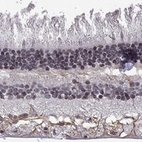

Immunohistochemical staining of human retina shows strong cytoplasmic positivity in nerve fiber layer.